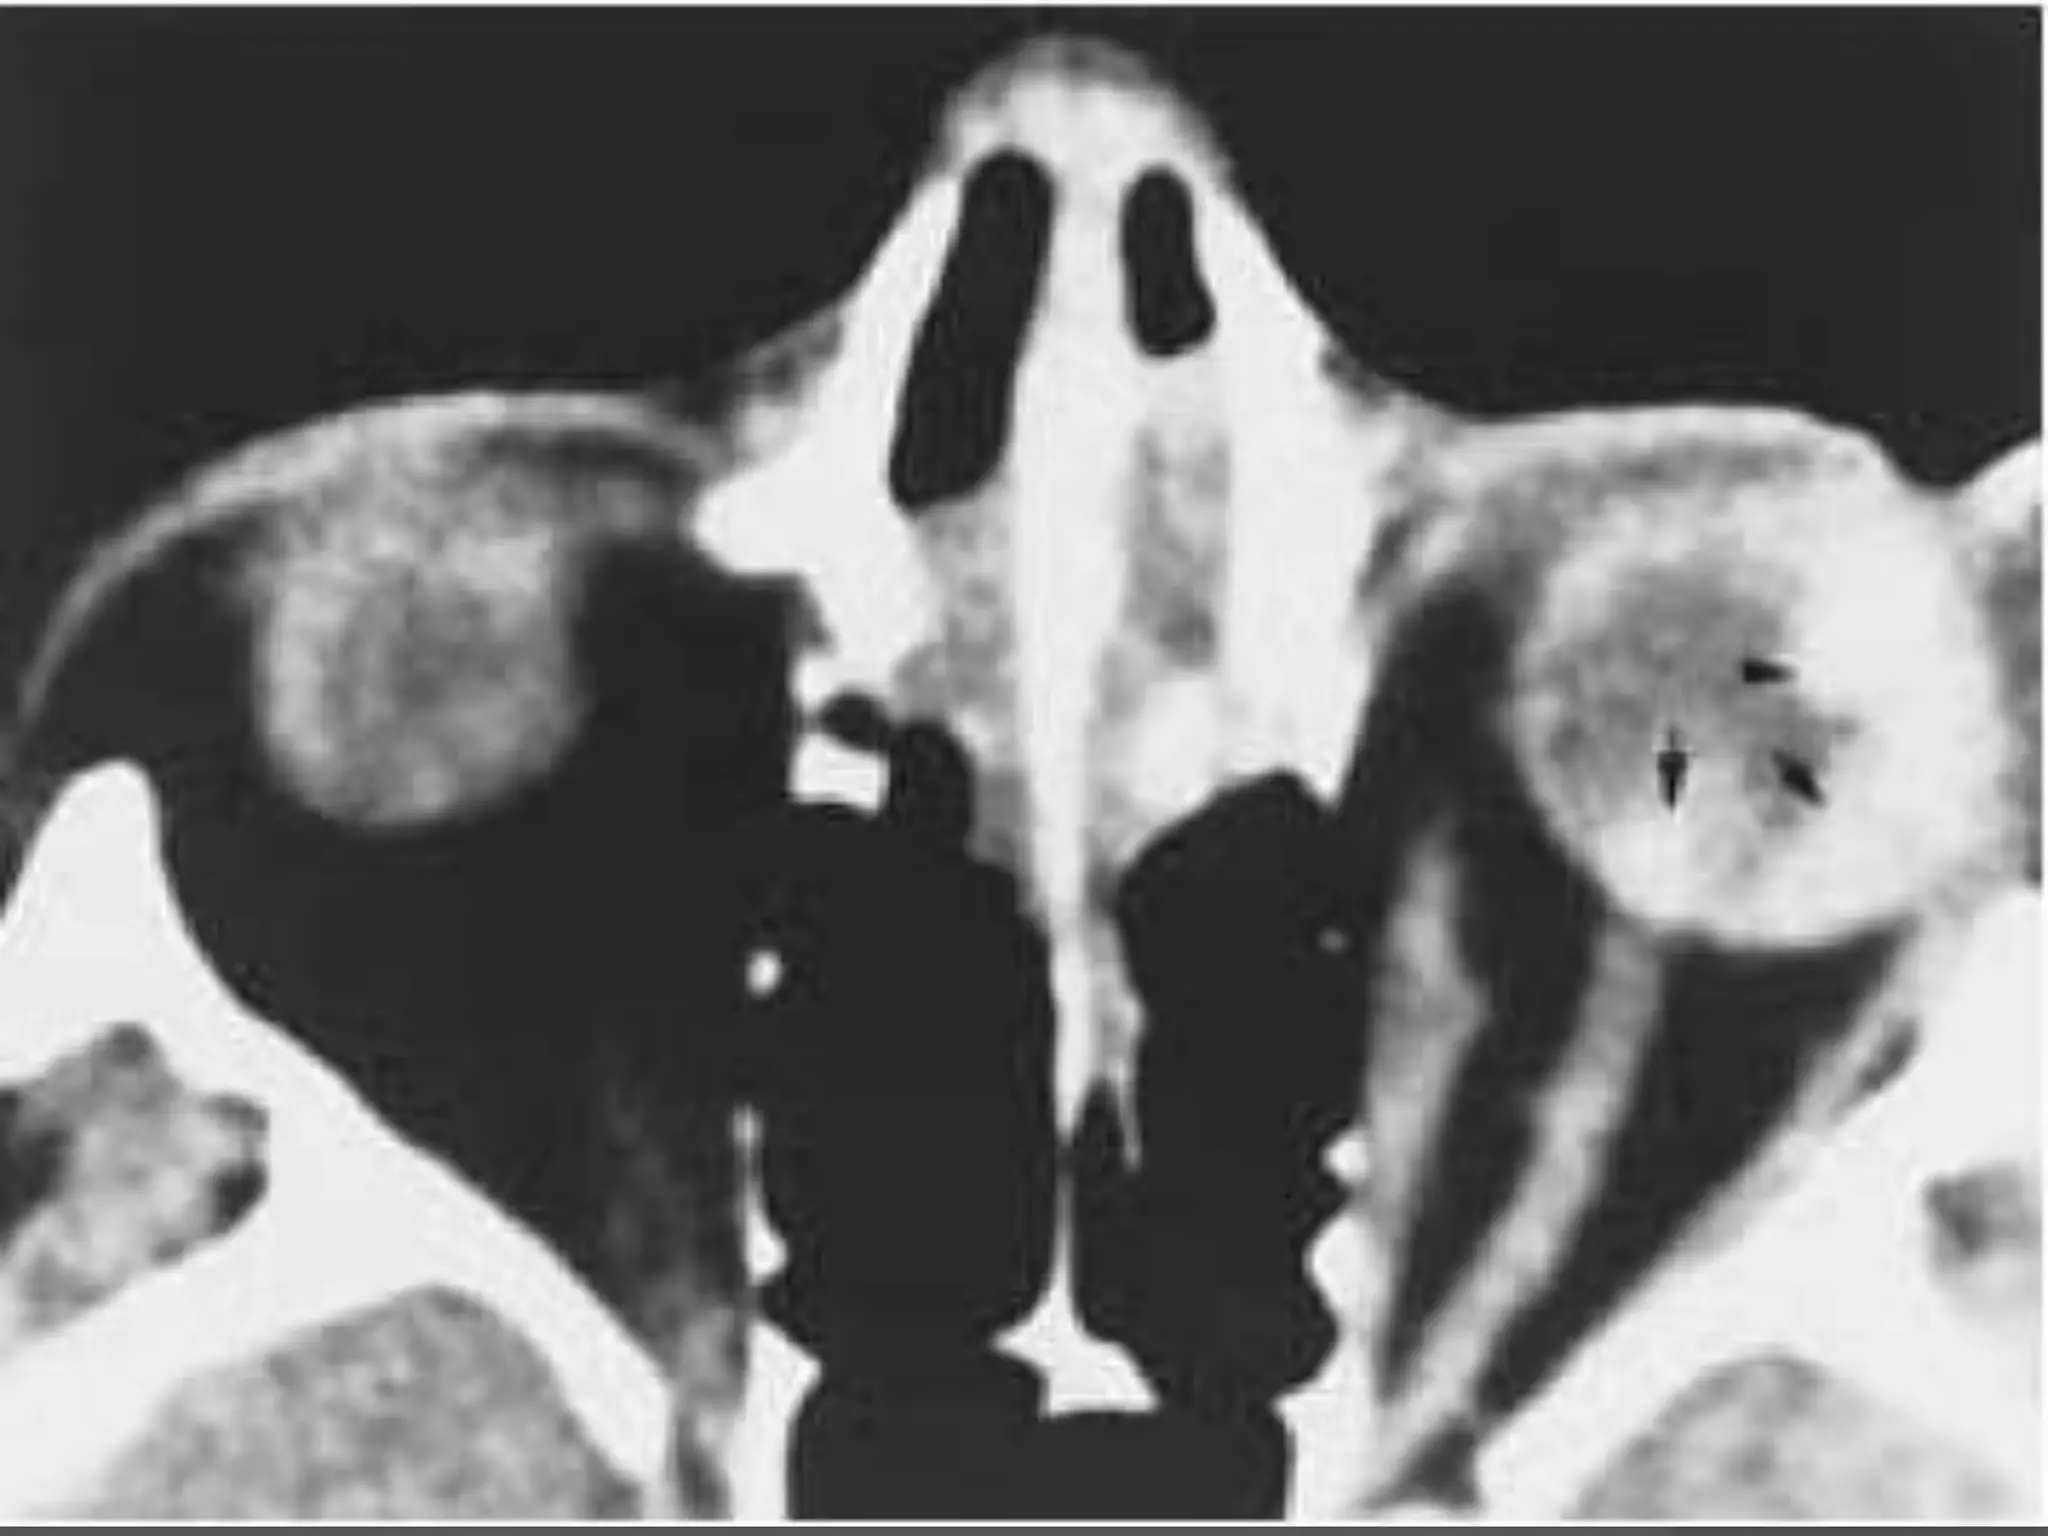

• #33 Coats’ disease. A, Axial CT scan shows generalized increased density of the left globe caused by bullous retinal detachment. The leaves of the detached retina are faintly seen, as shown by the arrows. B, Axial PW MR image shows hyperintensity of the left globe caused by subretinal lipoproteinaceous effusion. Note the leaves of the detached retina (arrows). C, Axial T2-weighted MR image shows the detached retina (arrows).